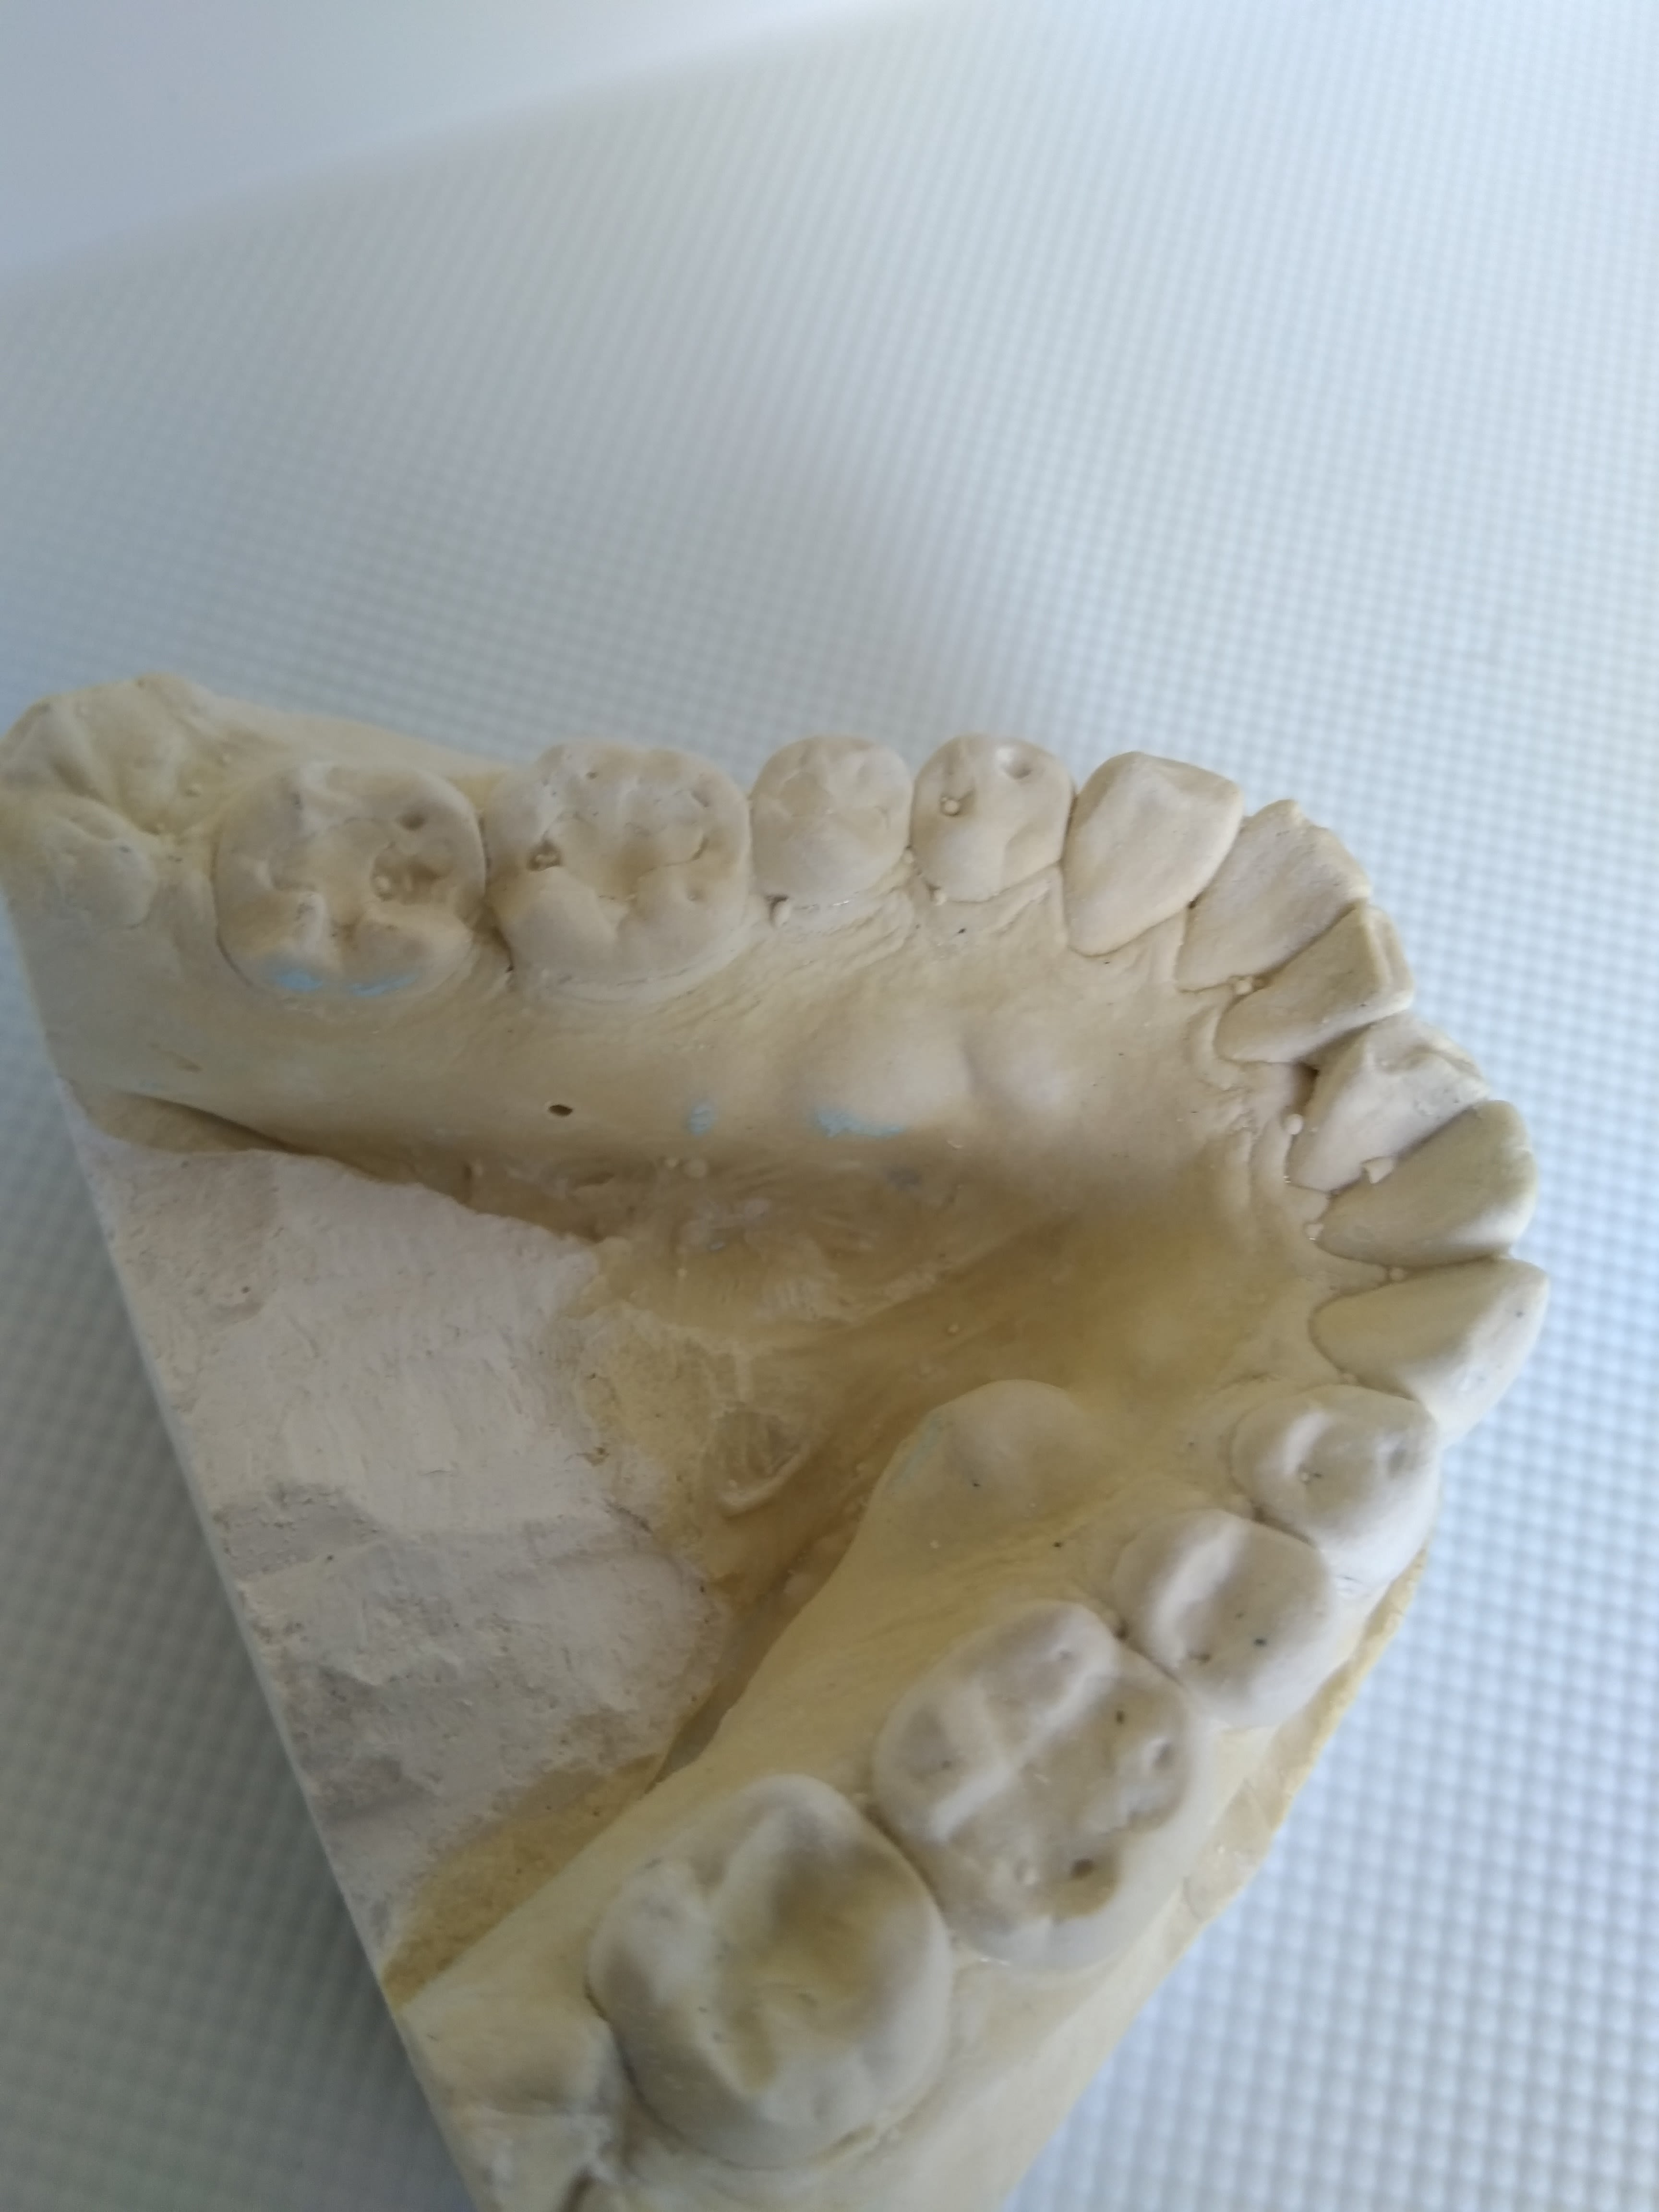

Jolis tori... c'est une femme, quand elle serre, elle serre.

Vue de dessus.